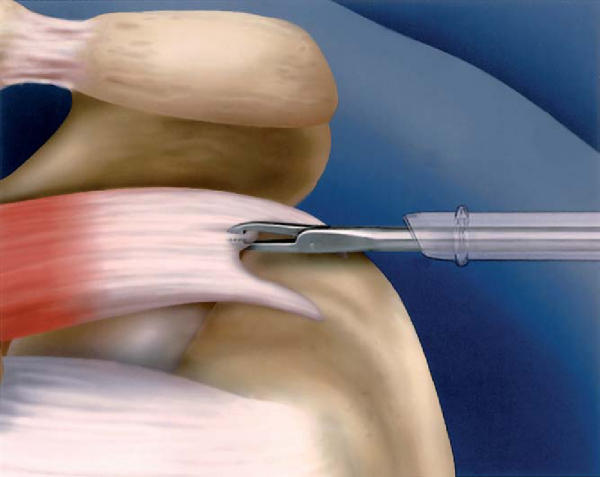

Suture Shuttle Through Lateral Anchor

Techniques have been developed to make suture bridges that are equivalent to transosseous tunnel compression stitches. Several variations exist to form a suture bridge, and early methods made use of existing implants and instruments. The medial suture anchors are placed as previously described for a double-row technique. One suture from each anchor is placed in a horizontal mattress fashion. The second suture limbs from each anchor are then passed together just medial to the horizontal mattress sutures. This not only makes a suture bridge but also approximates a modified Mason-Allen suture construct. Either one or two lateral suture anchors may be placed just lateral to the edge of the greater tuberosity (

Fig. 17-12

). After all sutures are passed, the horizontal mattress sutures are tied. One limb from the medial compression suture and one suture from the lateral anchor are retrieved outside the lateral cannula. The suture from the medial anchor is then sewn through the lateral suture with a free needle (

Fig. 17-13

). The lateral suture, acting as a shuttle with the medial suture attached to it, is pulled through the eyelet. A second suture may be shuttled through each anchor to make a cruciate-type suture bridge, if desired, to enhance the repair (

Fig. 17-14

). After the sutures are shuttled, knot tying is performed (

Fig. 17-15

).